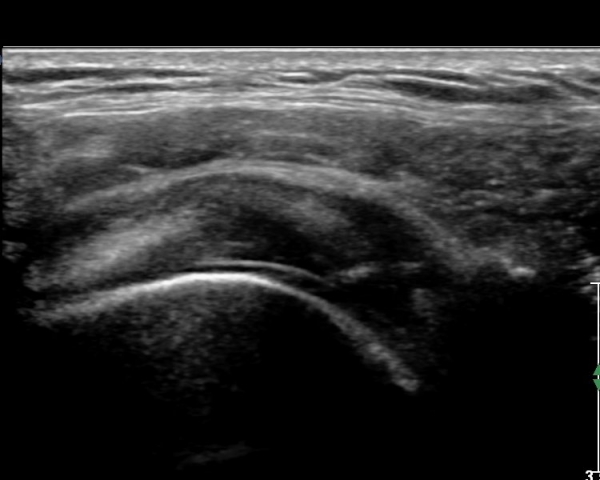

ŽÃËÀÚ¸¦ Á»´õ ¸»´ÜÀ¸·Î À̵¿ ÈÄ(¶Ç´Â ¾Æ·¡·Î ±â¿ïÀÎ ÈÄ) ³»ÃøºÎ¸¦ Á¶ÀýÇÏ´Ï °ß°©ÇÏ±Ù°Ç Ç¥ÃþÀ¸·Î Á¡¾×³¶³» ¼ö¾×Àú·ù°¡ °üÂûµÈ´Ù(»çÁö 3, 4). ŽÃËÀÚ¸¦ Á¶Á¤ÇÏ´Ï ÀÌµÎ¹Ú°Ç ÁÖÀ§ ¼ö¾× Àú·ù¿Í Á¡¾×³¶³» ¼ö¾×Àú·ù°¡ °üÂûµÇ¾î Á¡¾×³¶¿°°ú Ȱ¾×¸·¿°ÀÌ ÀÖÀ½À» ¾Ë ¼ö ÀÖ´Ù(»çÁø 5).

ŽÃËÀÚ¸¦ ¾à°£ ¿ÜÃøÀ¸·Î À̵¿ÇÏ¿© Á¶ÀýÇÏ´Ï À̵ιڰÇÀÌ °üÂûµÇ°í(»çÁø 6) ¾à°£ ¸»´ÜÀ¸·Î À̵¿ÇÏ´Ï °ÇÁÖÀ§ ¼ö¾×Àú·ù°¡ °üÂûµÈ´Ù(»çÁø 7). Á߸³À§¿¡¼ ŽÃËÀÚ¸¦ ¾î±ú ¿ÜÃø¿¡ ´ë°í °ßºÀ°ú ´ë°áÀýÀÌ ¸ðµÎ º¸À̵µ·Ï Á¶ÀýÇÏ¿© ¿ÜÀüÇÏ¸é¼ Ãæµ¹ ¿©ºÎ¸¦ °üÂûÇÑ´Ù. Á¤Áö »óÅ¿¡¼ ´ë°áÀýÀÇ °ñ °á¼ÕÀÌ °üÂûµÇ¾î ¸¸¼ºÀûÀÎ Ãæµ¹À» ½Ã»çÇÑ´Ù(»çÁø 8). ¿ÜÀü½Ã »ó¿Í°ñµÎ°¡ »ó¹æÀ¸·Î ¿òÁ÷ÀÌ°í °ßºÀ°ú Ãæµ¹ÇÔÀÌ °üÂûµÈ´Ù(»çÁø 8, ÷ºÎµ¿¿µ»ó 1).